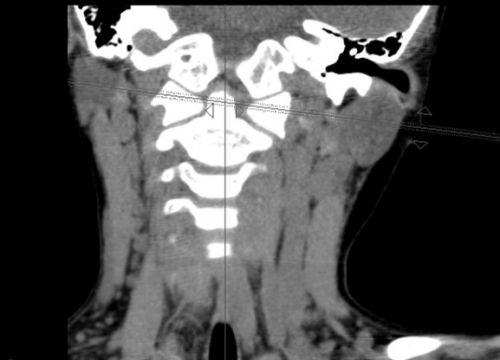

彬彬的影像检查显示:寰枢关节向左半脱位。

小儿骨科看急诊。医生为他进行了颈椎张口X光检查,被确诊为“寰枢关节半脱位”,当即收住院。经过六天的制动、牵引等治疗后,彬彬的病情有所好转。